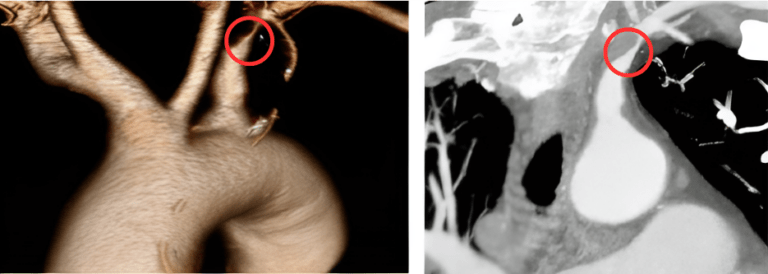

Bệnh nhân được chỉ định chụp CTA dựng hình hệ động mạch cảnh và đốt sống thân nền hai bên với kết quả hẹp # 70-80% đoạn gần động mạch dưới đòn trái, trước chỗ chia động mạch đốt sống trái do xơ vữa vôi hóa và kéo dài một đoạn 10mm.

Hình 4. Hình ảnh chụp CTA dựng hình hệ động mạch cảnh và đốt sống.